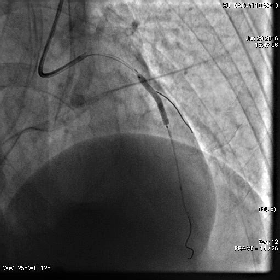

冠脉造影(右冠)

◆左主干未见斑块及狭窄,前降支近段可见斑块,狭窄约50-60%,中段分出第二对角支后完全闭塞,血流Timi0级,回旋支中段及远段斑块,狭窄约80-90%,血流Timi3级,右冠全程管壁不规则,斑块狭窄约30-40%。

急诊PCI小插曲

未见心包积液

血流Timi3级、分支都在